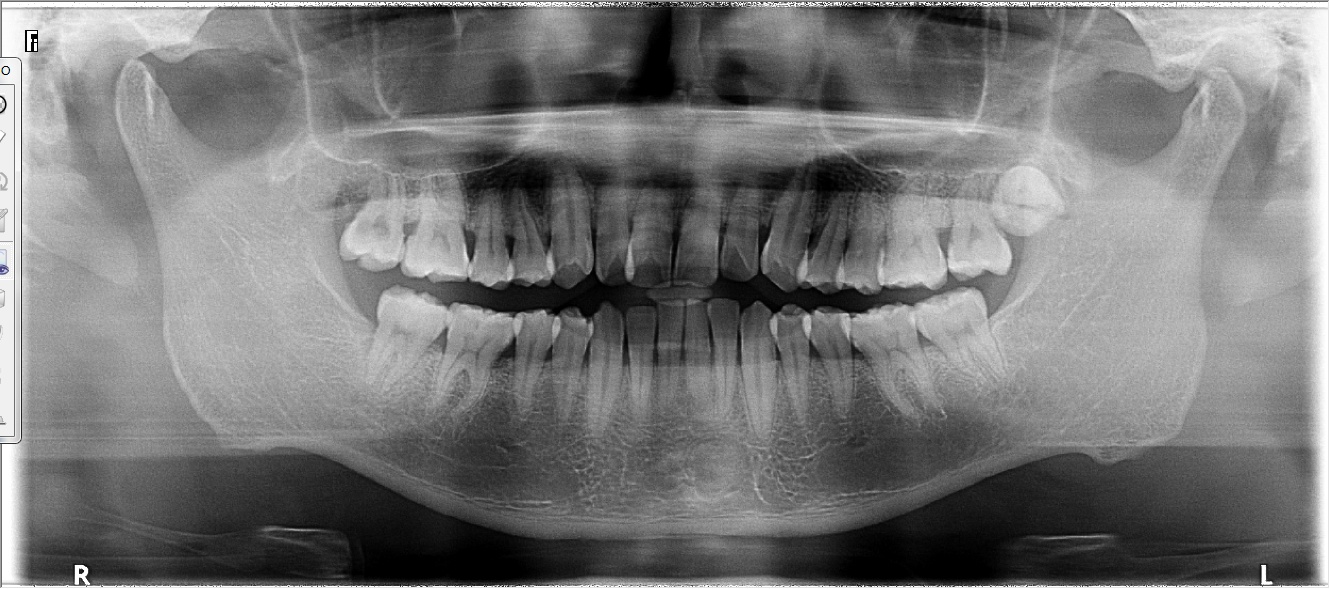

Carestream CS9000C Máy Chụp X-quang Nha Khoa Toàn Cảnh + Sọ Nghiêng Đã Qua Sử Dụng

Máy X-quang toàn cảnh + đầu dò sọ nghiêng đã qua sử dụng

Carestream CS9000C là hệ thống chụp ảnh toàn cảnh và sọ nghiêng kỹ thuật số hiệu suất cao đến từ thương hiệu Carestream Dental nổi tiếng toàn cầu. Được thiết kế để đáp ứng nhu cầu của nha khoa tổng quát và chỉnh nha, máy kết hợp hình ảnh kỹ thuật số rõ nét với công nghệ chụp sọ nghiêng one-shot — chụp toàn bộ hình ảnh chỉ trong một lần phơi sáng, mang lại kết quả nhanh chóng và ổn định.

✅ Chụp toàn cảnh & sọ nghiêng: Đáp ứng nhu cầu chẩn đoán toàn diện cho khám nha khoa hàng ngày và lập kế hoạch chỉnh nha.

✅ Hình ảnh kỹ thuật số độ phân giải cao: Hình ảnh sắc nét, chi tiết phục vụ đánh giá lâm sàng chính xác.